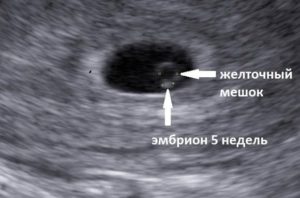

В ситуации, когда на УЗИ видно, что желточный мешочек есть эмбриона нет прогноз более благоприятный. Возможно, срок беременности не позволяет визуализировать сам эмбрион. В норме желточный мешок виден на УЗИ в период с 6 по 11 неделю беременности.

Касательно того, может ли быть желточный мешочек без эмбриона, то ответ зависит от того, что понимать, под словосочетанием нет зародыша.

Если его не видно, если он не развивается на момент, когда уже сформировался желточный мешок, но его размеры очень малы, то да – такая ситуация может быть.

Если желтое тело есть, а эмбриона нет (не путать с желтым телом яичника, речь идет о внезародышевом органе), то вероятность того, что эмбрион просто не разглядели — достаточно высока. Так как по сути желток обязан питать зародыш в первые три месяца. Одной из причин анэмбрионии является недоразвитость, ранняя редукция или полное отсутствие желточного мешка.